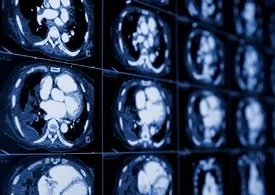

该系统扫描的层面厚度为0.5 mm,且三维扫描,这相当于将乳腺从上到下、从左到右、从表面到深部三维方向均切成厚0.5 mm的薄片,然后一片一片进行认真观察。因其所采集的图像为乳腺全视野的三维容积成像,几乎每个细节及局部(>5 mm)都能观察得到,诊断当然也就更精确了(图3)。

图3 乳腺增生ABVS超声图像

乳腺从皮肤至深部逐层扫描冠状切面图(黄色点处为乳头),层距厚0.5 mm;左图偏向扫描乳腺内侧,右图偏向扫描乳腺外侧,两者结合可避免遗漏。